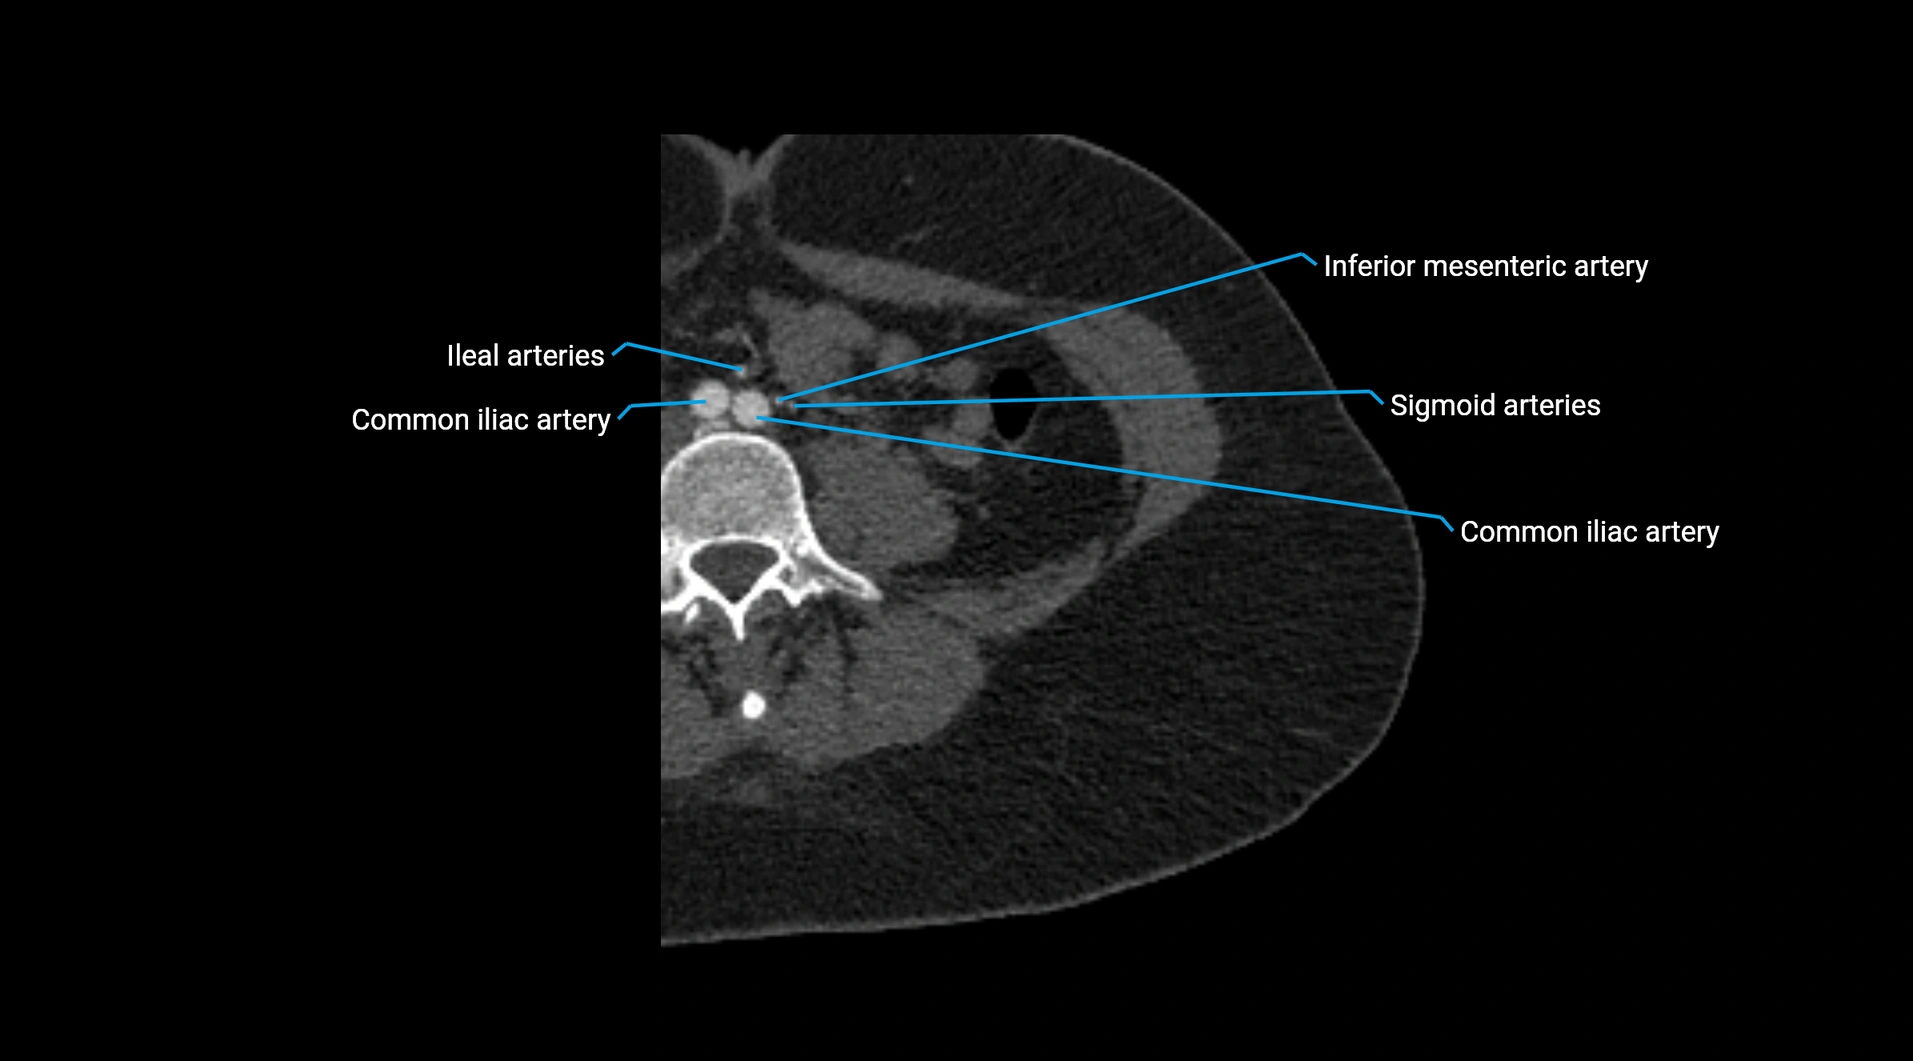

CT images

image